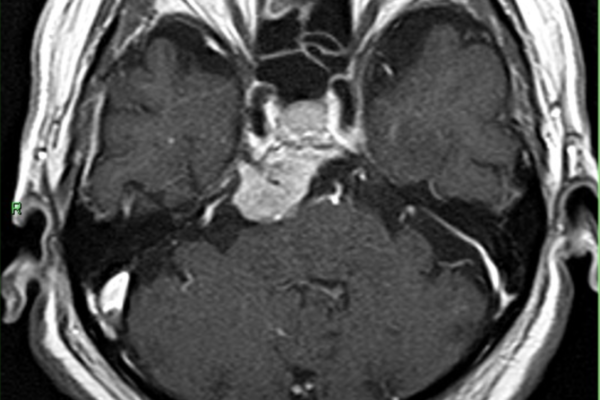

この腫瘍は聴神経から発生する良性の腫瘍(神経鞘腫)で、小脳橋角部という部分に発生するものです。聴神経には聴覚に関係する神経(蝸牛神経)と平衡感覚に関する神経(前庭神経)があり、前庭神経から発生するものが多いとされています。